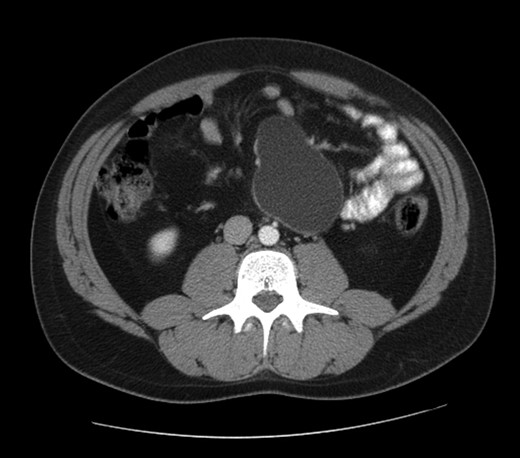

A 30 year-old man presented with diffuse abdominal pain in the last 6 months, without other abdominal or systemic symptoms. At the physical examination, a rounded swelling in the upper left quadrant was appreciated. The abdominal ultrasonography confirmed a rounded cystic formation, with regular walls, in the mesogastric region. A computed tomography scan showed a cystic mass measuring 95 × 60 mm, interjected between jejunal loops and located close to the inferior mesenteric artery and aorta (see Fig. 1).

The abdominal computed tomography scan with contrast revealed a huge (10 cm of diameter) retroperitoneal cyst, oval shaped and containing dense fluid, located within the caval vein and the aorta, under the origin of the renal artery, partially dislocating the caval vein to the right (see Fig. 2).

Computed tomography view of the mesenteric cyst partially dislocating the caval vein.